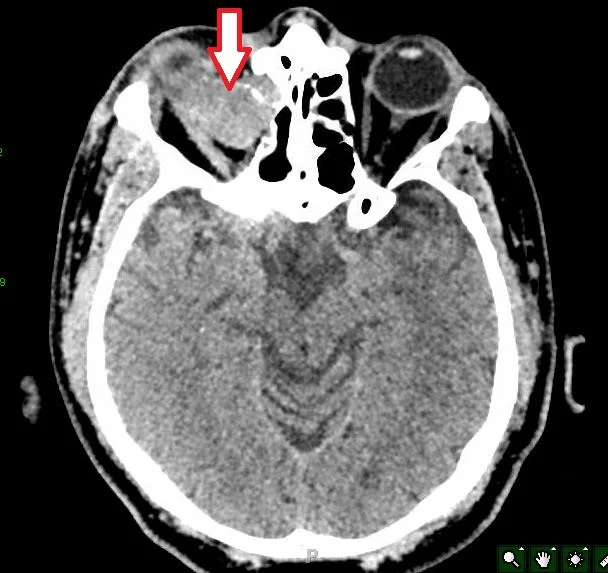

A 45 y.o. male presents with proptosis of the R eye his CT and MRI are shown below

Our patient had a mucocele which is an accumulation of mucoid secretions and desquamated epithelium within a sinus.  In this case it was cause by retained sinus lining after his frontal sinus fracture. He was sp cranialization of the R frontal sinus after his injury.  Over the course of many years he developed  a large mucocele intracranially but extradurally that displaced the globe and caused proptosis.  These may develop very slowly and can be reported 10 to 15 years after the fracture.  They can also occur without trauma in an obstructed sinus.

proptosis with a R frontal sinus mucocele

The frontal sinus is most commonly involved  in mucocele formation  with only rare mucoceles in the sphenoid, ethmoid and maxillary sinuses. The frontal sinus  is shared with the  superior orbital wall which explains the proptosis as the mucocele enlarges.